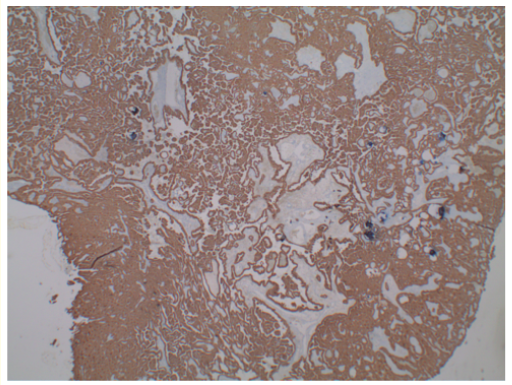

Idiopathic Granulomatous Mastitis - Experience in Two Australian Hospitals

Matthew Ng, Zarif Yahya, Michael Issac and Grace Chew. 6(5): 76-83.